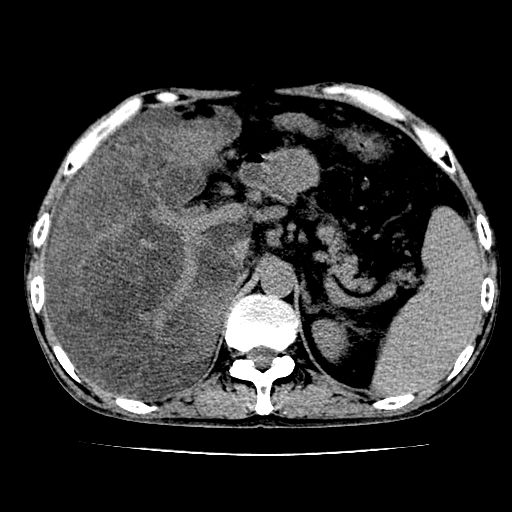

男,55岁,发现“肝硬化”5年,现腰疼、腹胀10余日,巩膜黄染、腹稍胀,肝肋下3指,质硬无压疼,移动性+,血生化:总胆、直胆、间胆均升高。

g1:肝硬化、脾大、腹水。

2:脂肪肝。

3:弥漫性肝癌待排。

肝硬化,脾大,腹水

脂肪肝

肝内多发低密度灶(建议增强扫描除外肝癌)

肝脾肿大,脂肪肝,腹水。建议增强除外肝癌。